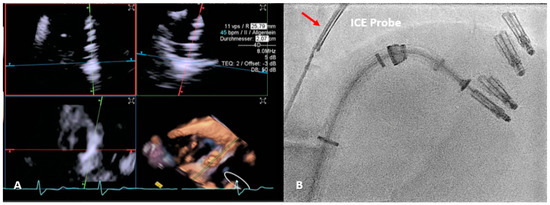

However, TEE guiding is often not avoidable, such as during valve repair or replacement interventions [24]. This is frequently not feasible in the transcatheter context, so alternative approaches must be considered. Specifically, the mini 3D TEE probe can be used in these circumstances [44]. Patients suffering from esophageal stricture can also benefit from this option. For optimal intraprocedural imaging, intracardiac echocardiography (ICE) may also be a useful tool (Figure 2). Due to its ability to produce high-resolution near-field imaging, ICE can overcome TEE limits, such as acoustic shadowing, and avoid GI or respiratory complications. However, the high expense of this technology severely restricts the application of ICE in routine clinical practice [62,63,64].

Figure 2.

ICE application during T-TEER. (A) illustrates the live multiplanar reconstruction process used to align the TriClip (Abbott Vascular, Santa Clara, CA, USA) device on the tricuspid valve, for grasping the anterior and septal leaflets. In (B), the fluoroscopic position of the intracardiac probe can be observed (red arrow). The proximity of the probe to the device allows us to overcome shadows by obtaining high-quality images. T-TEER: Tricuspid Transcatheter edge-to-edge repair; ICE: intracardiac echocardiography.